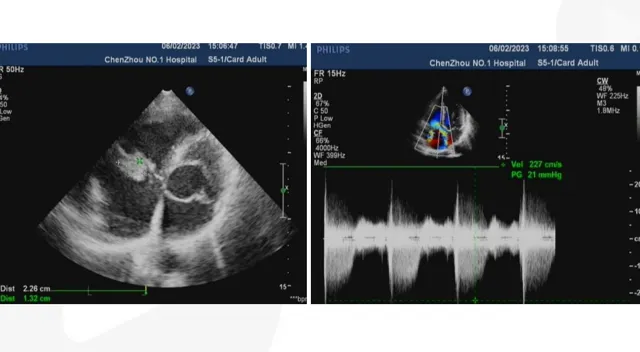

上面展示的兩個心內膜炎病例,你會看嗎?想看更多心臟超聲內容(如房間隔缺損、室間隔缺損的超聲診斷)嗎?